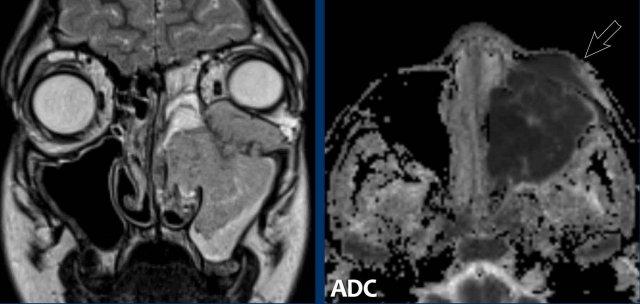

Các hình ảnh này của một bệnh nhân nam 16 tuổi với biểu hiện lồi mắt và chảy máu mũi.

Trên các hình ảnh này, có một tổn thương phá hủy xương với xâm lấn vào hốc mắt.

Tiếp tục xem các hình ảnh MRI…

MRI cho thấy một khối u phá hủy một bên với hạn chế khuếch tán rõ rệt (giảm tín hiệu trên bản đồ ADC).

Như vậy, chúng ta có ba dấu hiệu cảnh báo.

Hạn chế khuếch tán là một lập luận khác chống lại chẩn đoán u xơ mạch máu vị thành niên, vì một tổn thương mạch máu sẽ không gây ra hạn chế khuếch tán.

Có xâm lấn vào hốc mắt và cả vào phần mềm phía trước của má (mũi tên).

Sinh thiết được thực hiện và cho kết quả là u cơ vân (rhabdomyosarcoma), được điều trị bằng hóa trị liệu.